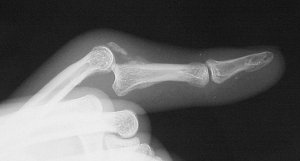

The most common type of middle phalanx base fracture is a small volar plate avulsion fracture, which commonly accompanies a sprain or dislocation of the proximal interphalangeal joint. This usually heals with a painless fibrous union. This injury requires no specific treatment other than what is indicated for the associated joint injury. Less common but much more troublesome are fracture-dislocations of the proximal interphalangeal joint. If the fracture line extends through the proper collateral ligament, the joint will become unstable, and the middle phalanx will displace with subluxation. Dorsal fracture-dislocations with a large palmar fragment are more common than volar fracture-dislocations. Either can be complicated by central articular impaction (Fig. 3). Treatment is controversial with advocates for internal or external fixation using a variety of techniques, including dynamic external traction, external fixation with distraction, internal fixation, and joint reconstruction with an osteochondral graft. Common principles include correction of subluxation, bone graft to correct impaction, and early motion.